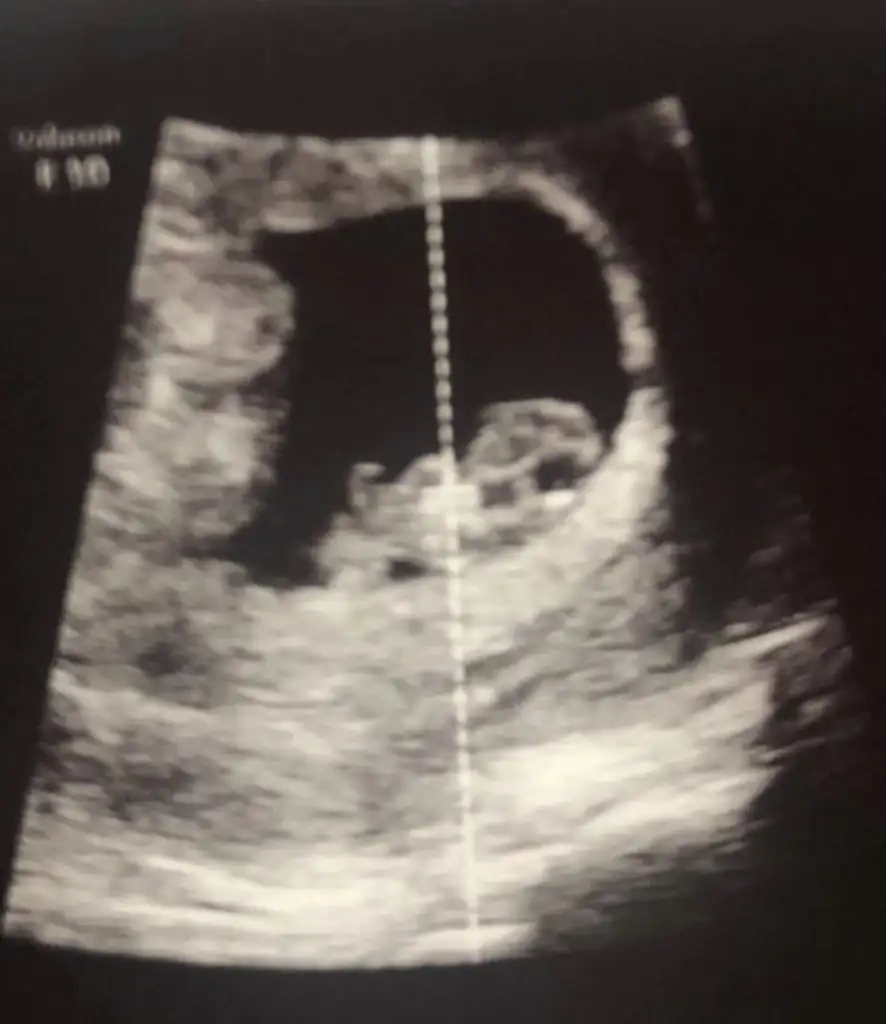

dr soylemeden siz gorun genital nub teorisi ( bebegin cinsiyeti)

Nub bilen var mi kizlar

Arkadasimin bebisi cok merak ediyor

Banada tahmin yaparmısınız ?